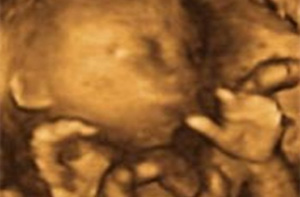

Embarazo semana 19: Se puede saber el sexo del bebé

Cerebro y médula espinal siguen desarrollándose durante la semana 19 de embarazo. Durante estos días, el cuerpo del bebé sufre muchos cambios (a mejor) y tú también notas transformaciones físicas, como cambios genitales o palpitaciones. Esta semana ya te pueden hacer la famosa ecografía morfológica, que se suele realizar en torno a la semana 20 de gestación. En el ultrasonido es posible ver los genitales engrosados del bebé.

Es en esta ecografía donde suele ver claramente el sexo del feto, ya que en la anterior, realizada en la semana 12 de embarazo en los hospitales públicos, aún es muy pronto para este diagnóstico.

- Mide entre 13 a 15 centímetros y ya pesa unos 200 gramos. Cada día que pasa va adquiriendo un aspecto más humano.

Los genitales aparecen engrosados al visualizarlos en ecografía.

La llamada ecografía morfológica se realiza se realiza en entre la 18+0 y la 21+6 semanas de embarazo. En las gestantes obesas es preferible realizarla más cercana a las 21+6 semanas para poder visualizar mejor los diferentes órganos del feto. Es la del segundo trimestre -la segunda que se realiza en los hospitales públicos- y sirve para valorar la estructura y biometría fetal. Es decir, no sólo nos muestra las medidas ecográficas del feto, sino que también diagnóstica anomalías en el desarrollo fetal.